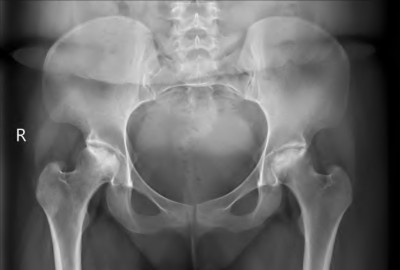

A 45-year-old female with developmental dysplasia of the hip (DDH) presents for THA. Preoperative radiographs show the femoral head is subluxated, with 80% proximal migration relative to the height of the normal true acetabulum. Based on the Crowe classification, what type of dysplasia does she have?